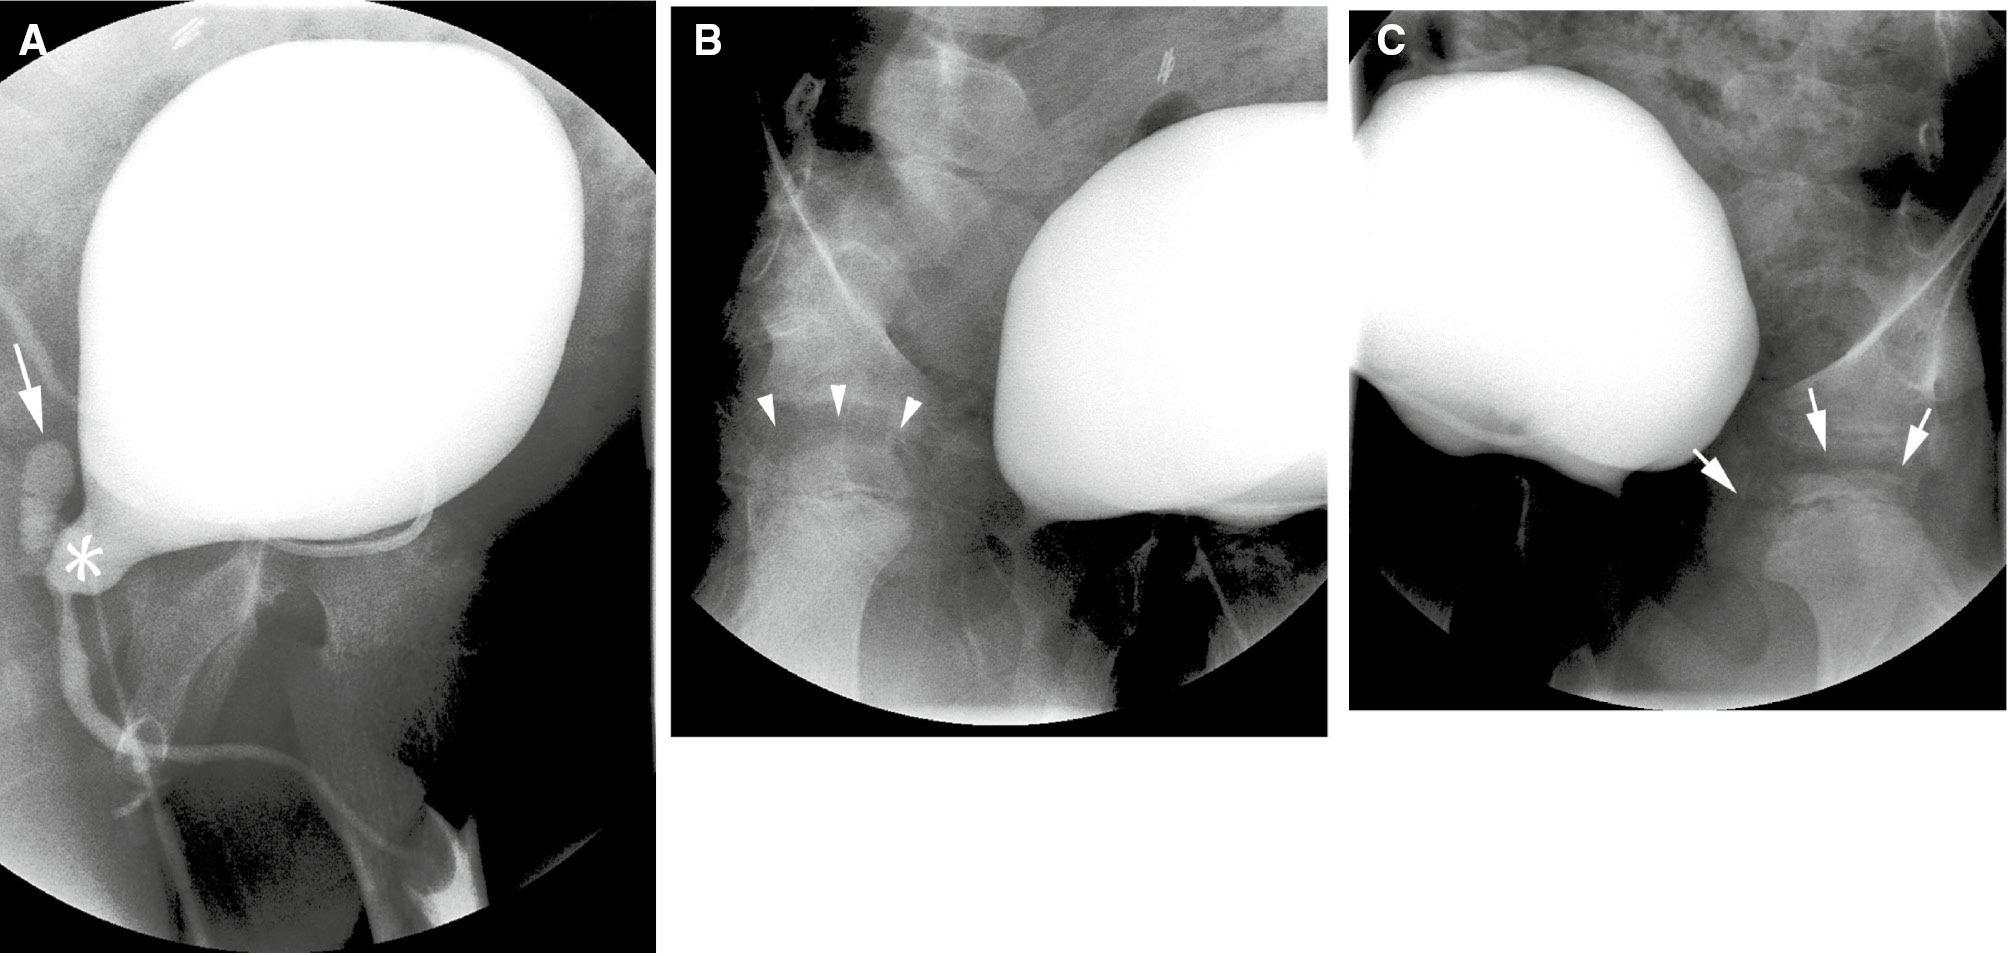

Figure 3: Inattentional blindness error.Voiding cystourethrogram in a 9-year-old male with treated posterior urethral valves. Three images from the study are shown. Oblique view of the bladder during voiding (A) shows a dilated posterior urethra (asterisk), and reflux into a dilated utricle (arrow). Right oblique view (B) of the bladder shows a normal femoral head (arrow heads). Left oblique view (C) shows sclerosis and fragmentation changes of the left femoral head due to avascular necrosis (arrows). This unexpected, but radiographically obvious finding was initially missed.

Figure 3:

Inattentional blindness error.

Voiding cystourethrogram in a 9-year-old male with treated posterior urethral valves. Three images from the study are shown. Oblique view of the bladder during voiding (A) shows a dilated posterior urethra (asterisk), and reflux into a dilated utricle (arrow). Right oblique view (B) of the bladder shows a normal femoral head (arrow heads). Left oblique view (C) shows sclerosis and fragmentation changes of the left femoral head due to avascular necrosis (arrows). This unexpected, but radiographically obvious finding was initially missed.

A second contributing factor to perceptual error is the phenomenon of inattentional blindness. The term was introduced by Mack and Rock in the 1990s, and is defined by the failure to notice a fully visible, but unexpected object because attention was engaged on another task, event, or object [19]. In one study, participants were asked to count basketball passes by players wearing white shirts and to ignore passes made by players wearing black. Approximately 50% of subjects watching the video did not notice a person in a gorilla suit entering the scene, stopping to face the camera and thump its chest before exiting on the other side [20]. Thus, if a finding is not expected on an imaging study, there is a strong likelihood that it will be missed (“I will see it when I believe it”). This phenomenon was shown in a study of 24 chest radiologists asked to identify pulmonary nodules in a stack of chest CT images. A gorilla, 48 times larger than the average nodule, was inserted in the last case. More than 80% of radiologists failed to see the gorilla. Of note is that failure to see the gorilla was not due to a truncated visual search. In fact, visual tracking of the radiologists showed that the majority of those who missed the gorilla had actually looked directly at the location of the gorilla [21] (Figure 3).